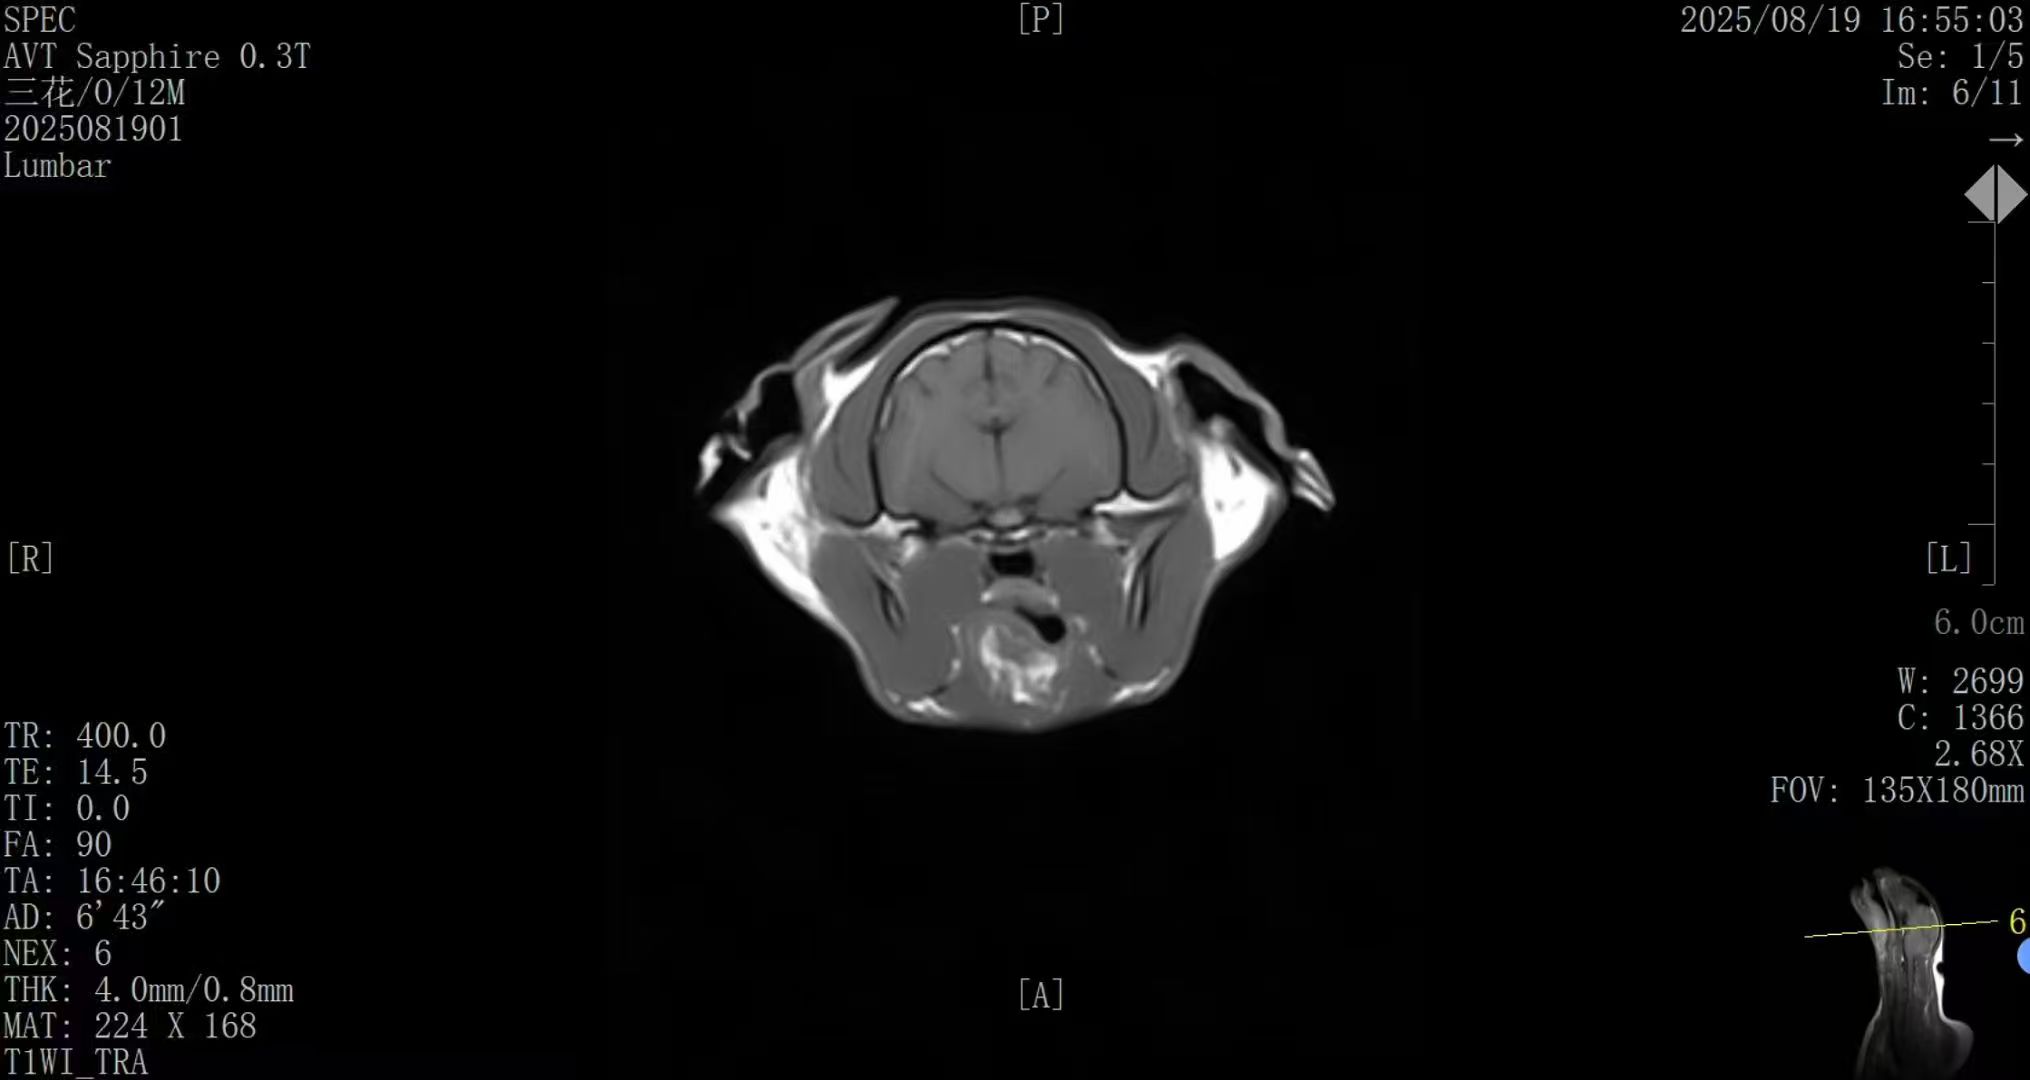

✅ AI智能成像 · 诊断更精准

搭载新一代AI影像优化系统,图像信噪比与组织对比度 整体提升约50%;

在神经、脊柱、关节及软组织等常见病例中表现优异,图像清晰、细节丰富,满足临床精准诊断需求。